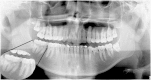

Fusion or gemination? An unusual mandibular second molar

Fusion and gemination is not an uncommon finding and affected most primary dentition and the permanent maxillary incisors. These changes can develop a series of complication. A 11-year-old male presented radiography finding: an unusual mandibular second molar. A well-documented case brings a challenge for radiologists classify between fusion and gemination. In conclusion, this alteration although common in other regions, there are no case in the literature involving "second and third" molar.